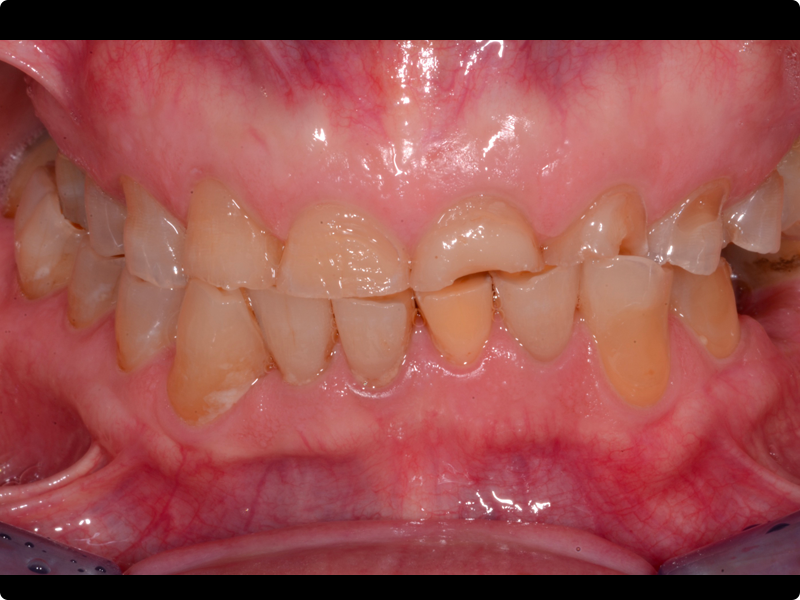

• Per anomalie di forma: amelogenesi imperfetta, MIH e denti conoidi

• Faccette:

• Sequenza completa di realizzazione: dalle foto iniziali alla cementazione

• Corona:

• Sequenza completa di realizzazione, sia dei casi semplici che di quelli complessi.